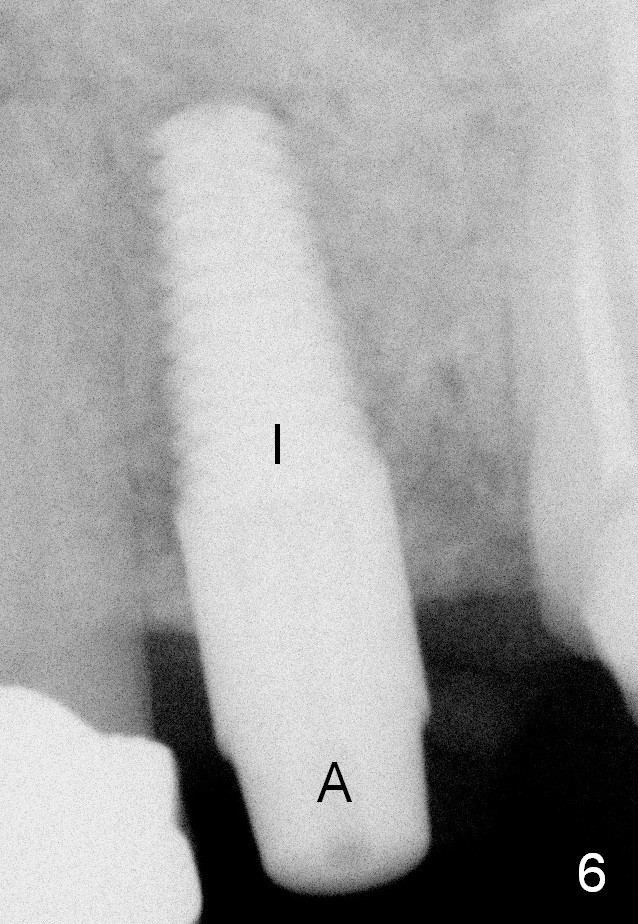

A 45-year-old lady is nervous about dental treatment. The missing tooth #13 was replaced by a 3-unit bridge. The latter is sectioned because the posterior abutment has caries. PA in Fig.1 is taken when root canal therapy and build up are finished. Fig.2 shows the wide edentulous area with a single-unit crown being tried in for #14. Osteotomy is initiated with the crown in place without cementation, since it is easy to determine the mesiodistal position (Fig.3 red lines). Without the crown in place, osteotomy tends to be distal. In this case, the osteotomy is later attempted to be moved distally with Lindamann bur and deepened to 14 mm from the gingival margin (Fig.4). A 2.5 mm reamer is being used at 50 RPM to increase osteotomy with difficulty. Drills have to used at high RPM instead (Fig.5 4x14 mm). A 4.5x14 mm tissue-level implant is placed with insertion torque >60 Ncm (Fig.6 I); a 4x3 mm abutment (A) is placed immediately for an immediate provisional. Fig.7 is taken 7 days postop to show the gingival recipient site formed by the provisional. The patient is so afraid of X-ray that the next one is taken 1.5 years post cementation (Fig.8). It appears that dense bone bundle forms between the crest and the 1st implant thread (adaptation functional change, arrowheads). The bone density continues to increase 2 years 8 months post cementation (Fig.9 *, 10); the bone has grown into the area between the 1st 2 threads (arrow).